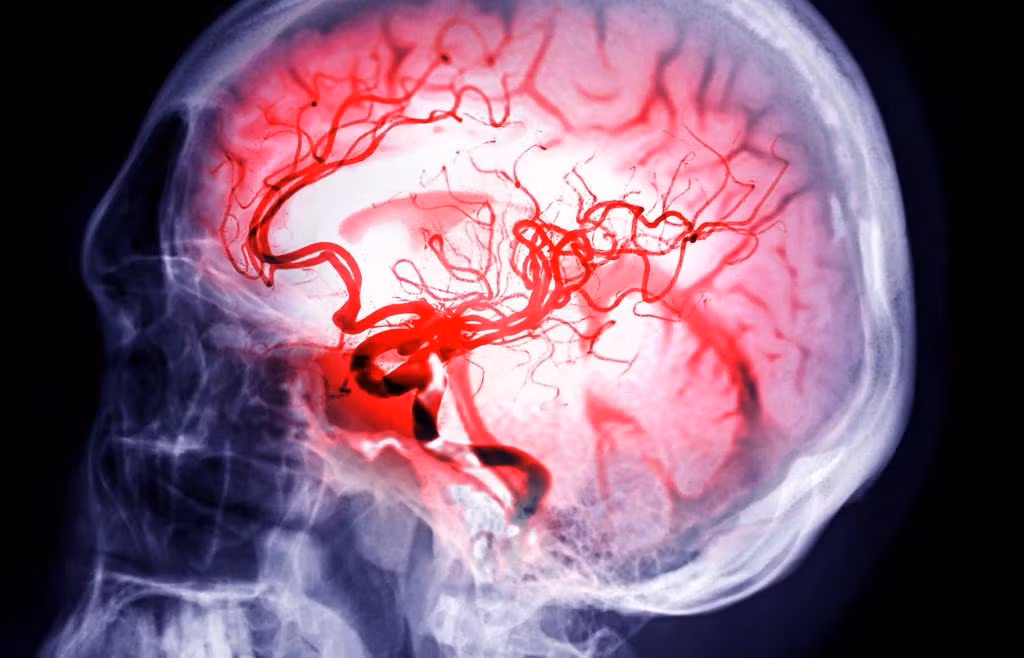

Tiến sĩ Stuart Hameroff, bác sĩ gây mê và giáo sư tại Đại học Arizona, gần đây đã thảo luận về một nghiên cứu ghi lại hoạt động não của những bệnh nhân chết lâm sàng có thể chứng minh linh hồn có thật. Ảnh: Getty Images.

Ông Hameroff giải thích cách các nhà nghiên cứu đặt các cảm biến nhỏ trên não của 7 bệnh nhân mắc bệnh mãn tính vài phút trước khi họ ngừng hỗ trợ sự sống, cho phép họ ghi lại hoạt động sau khi huyết áp và nhịp tim của mỗi bệnh nhân giảm xuống mức 0. Ảnh: The Project Unity.

Tiến sĩ Hameroff chia sẻ với người dẫn chương trình Jay Anderson trong chương trình YouTube Project Unity rằng, các nhà khoa học quan sát thấy “mọi thứ dường như biến mất nhưng sau đó lại có sự bùng nổ của hoạt động trong não. Đó có thể là trải nghiệm cận tử hoặc linh hồn rời khỏi cơ thể”. Ảnh: TheProjectUnity/X.

Đồng thời, Tiến sĩ Hameroff cho hay điều này có thể giải thích tại sao con người vẫn có nhận thức trong trạng thái não bộ có năng lượng thấp như gây mê, ngủ sâu hoặc thậm chí là trải nghiệm cận tử. Ảnh: TheProjectUnity/X.

Các nhà nghiên cứu cho biết lời giải thích khả thi nhất là các xung điện được giải phóng khi não bị thiếu oxy. Ảnh: samunella – stock.adobe.com.